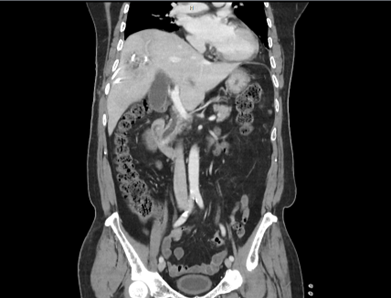

[그림 1] 간 우엽에 저음영 병변

환자의 임상 증세를 고려하였을 때 화농성 간농양(pyogenic liver abscess)으로 판단되었으며, 경피적 배액술과 경험적 항생제 (3세대 세팔로스포린계열) 치료를 시작하였다. 이후 임상 경과는 점진적으로 호전되었으나, 추적검사로 상태 안정된 후 조영제를 사용한 역동정 조영증강 CT 검사에서 총담관 확장 소견이 동반되어 [그림3] 추가적인 원인 평가를 시행하였다.